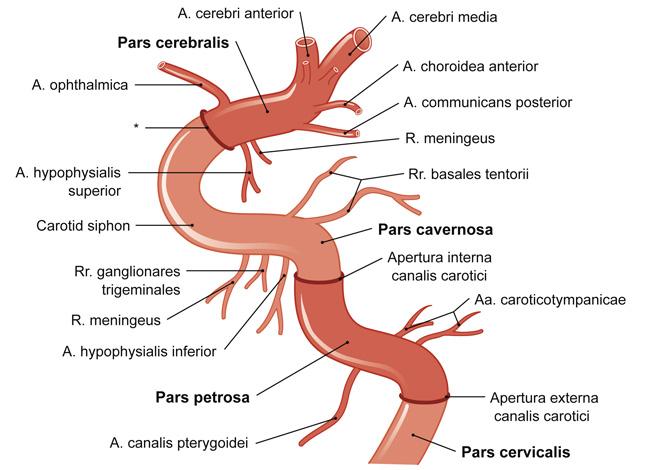

Fig 3.11: a. carotis interna

-

schedelbasis

-

a carotis communis

-

cirkel van Willis

details: zie neuro a vertebralis > a basilaris > a cerebri posterior a carotis interna > a cerebri media a carotis interna > a cerebri anterior a carotis interna > a communicans posterior a communicans anterior

|

|